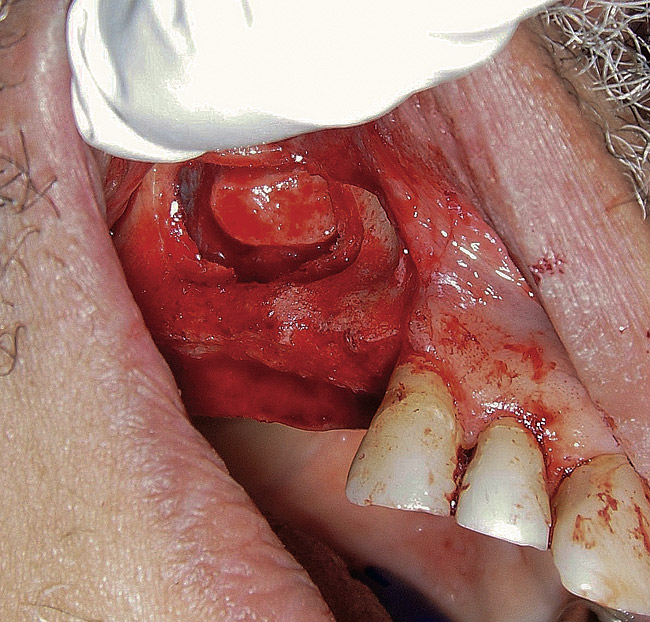

The lateral approach is also used for sinus floor elevation. It is indicated when there is reduced residual bone height, which does not allow standard implant placement or placement of implants in combination with minor sinus floor elevation using the osteotome technique (Figure 1, Figure 2 and Figure 3). Contraindications are excessive interarch distance due to unfavorable crown-to-root ratio, acute or chronic unresolved sinusitis, current sinus pathology (eg, cysts or tumors), lodged root tips in the sinus, history of heavy smoking, a systemic compromise, and psychological problems.

Figure  1  Elevation of the flap.

Figure 1